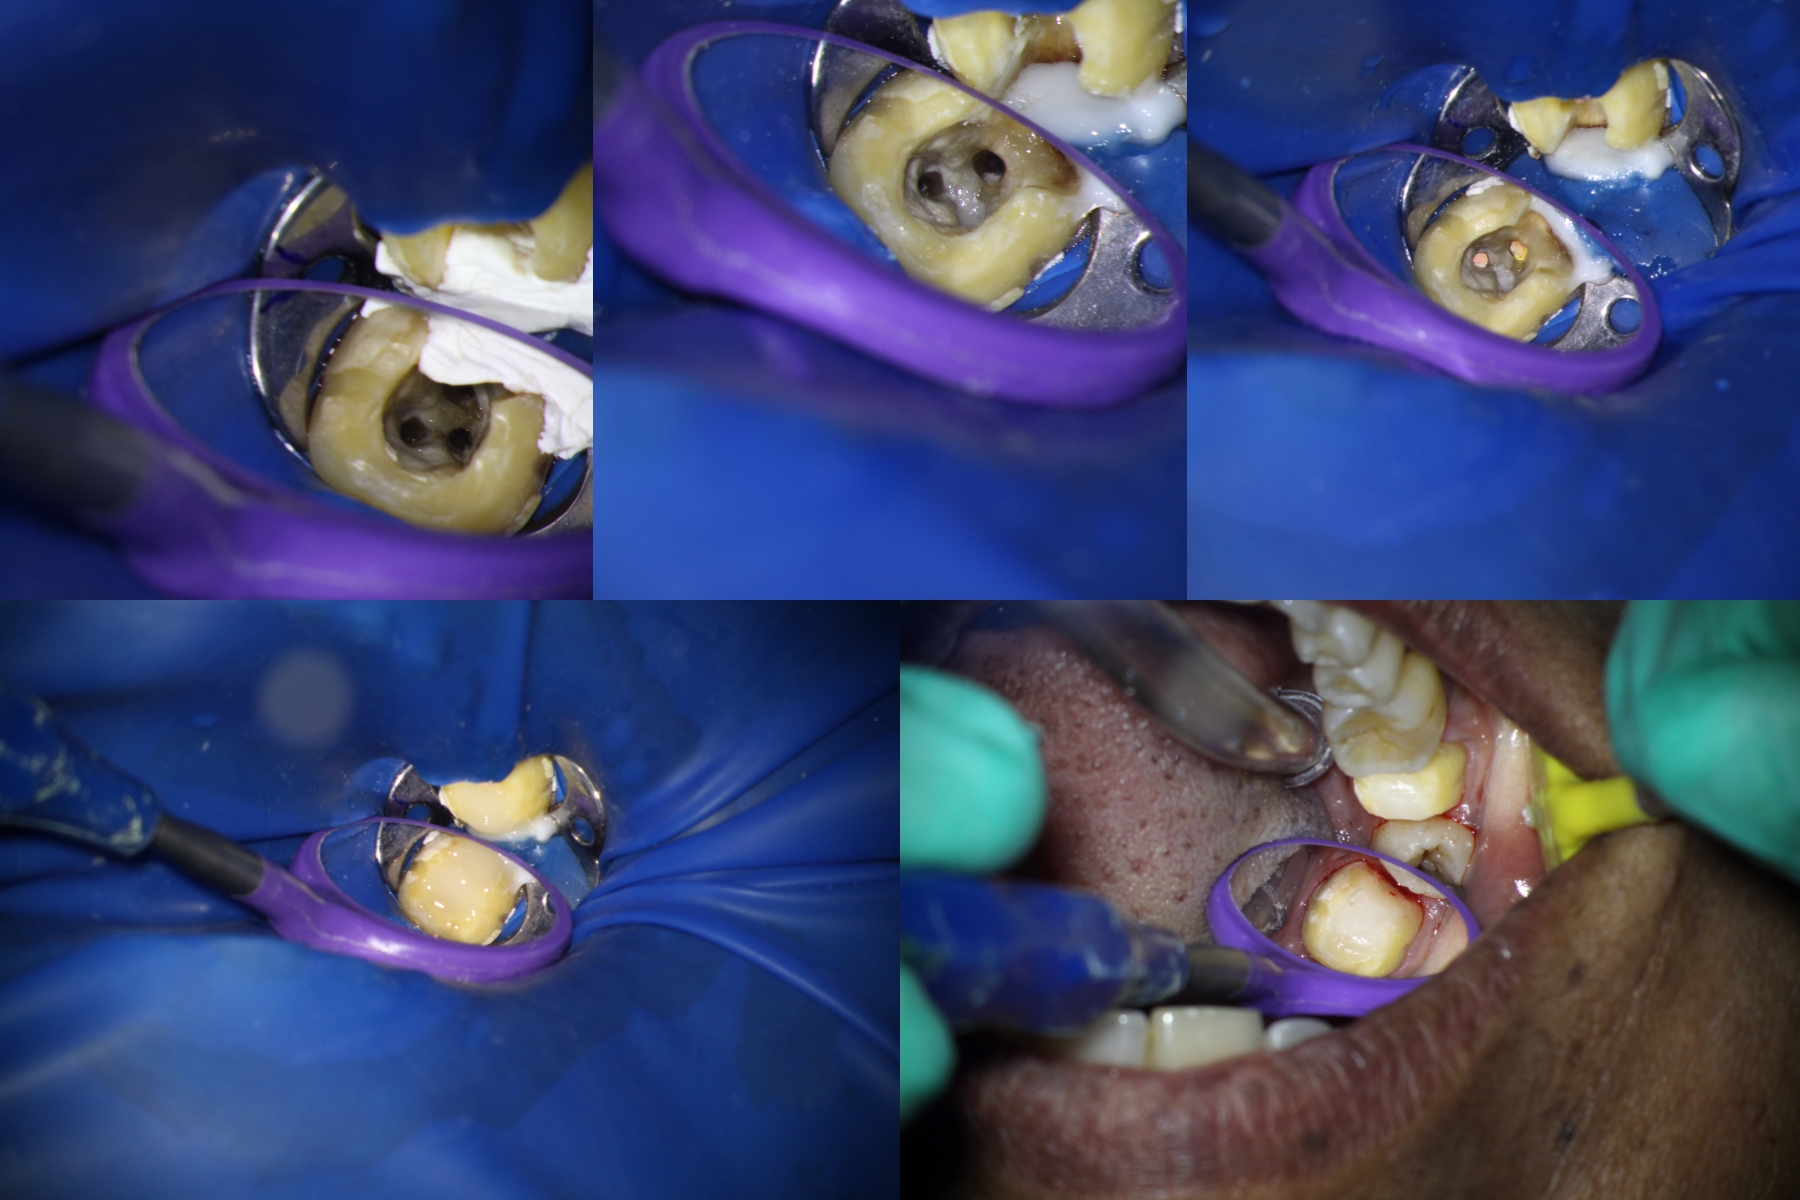

Pt 50 YOF presented with dislodged crown and severe pain in the recently RCT done #31. Started Re-treatment, after cleaning the chamber saw three orifices and finished the canals preparation, but was not sure of the distolinugal. I did not diagnose perforation as there was no bleeding nor patient complained of any pain during the preparation. Later Scan confirmed perforation and was sealed with fiber reinforced composite.